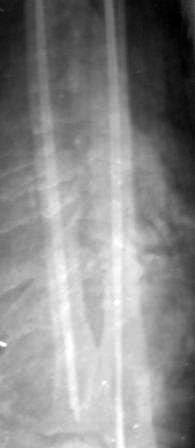

Пациентка 49 лет, по поводу перелома обеих костей предплечья оперирована в марте месяце « и/м остеосинтез спицами», через 4 месяца спицы удалены , антибиотикотерапия и фиксация гипсовой повязкой продолжена, но, учитывая что образуются ложный сустав, госпитализирована.

Повторно открывать зону перелома никак не хочется, учитывая р-картину! А что если закрыто рассверливать к/м канал ( как при БИОС), и КДО аппаратом Илизарова? Уважаемые коллеги помогите советом! Извиняюсь за плохое качество р-снимков!